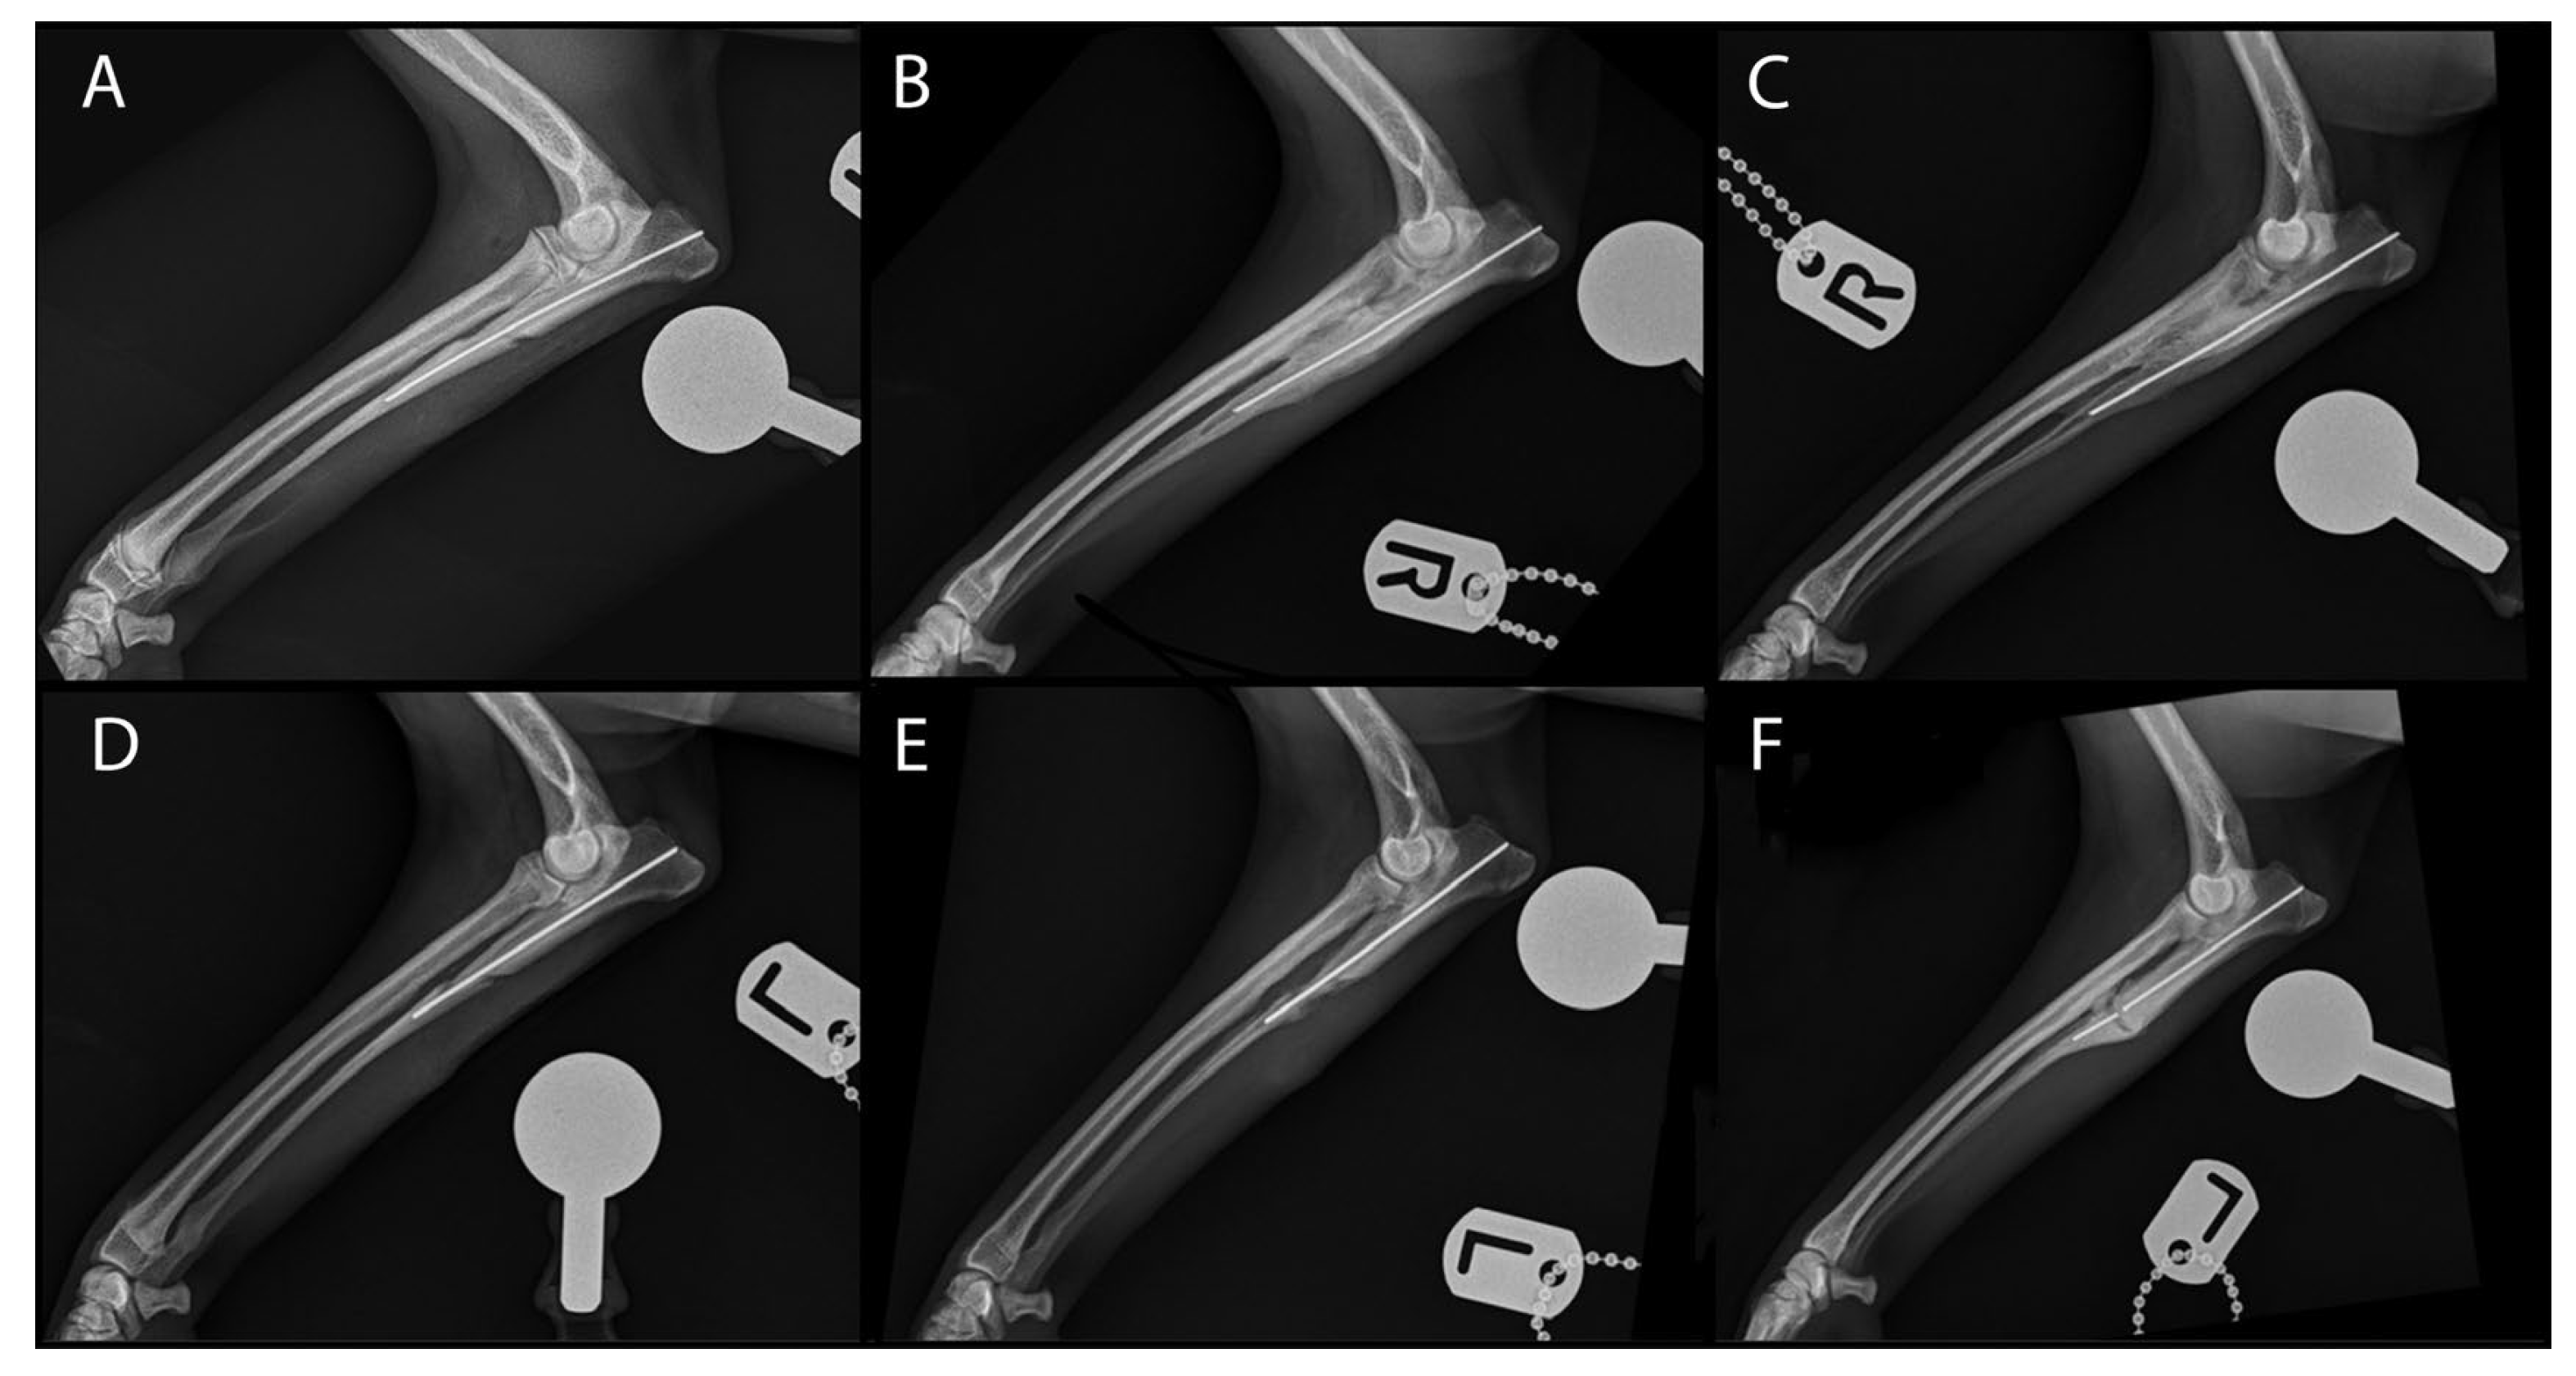

2. Materials and Methods

Surgical Treatment

3. Results